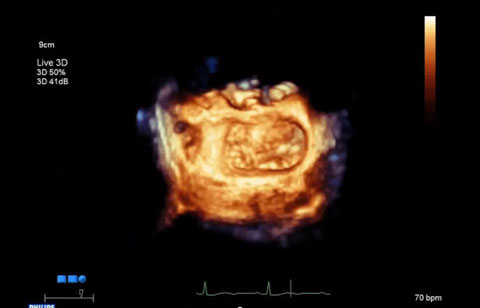

بعد تشخيص مريض بارتجاع الصمام الميترالي، ما هي خيارات العلاج المتوفرة له؟ إذا لم يكن مرشحًا للخضوع لعملية القلب المفتوح، يمكنك التفكير في معالجته عبر إصلاح الصمام الميترالي باستخدام القسطرة (TMVR). وفي يومنا الحالي، تؤمن حلول التصوير المبتكرة والأجهزة المتوفرة حديثًا خيارات جديدة لبعض المرضى.

التخطيط للإجراءات باستخدام البيانات الكمية الموثوقة.